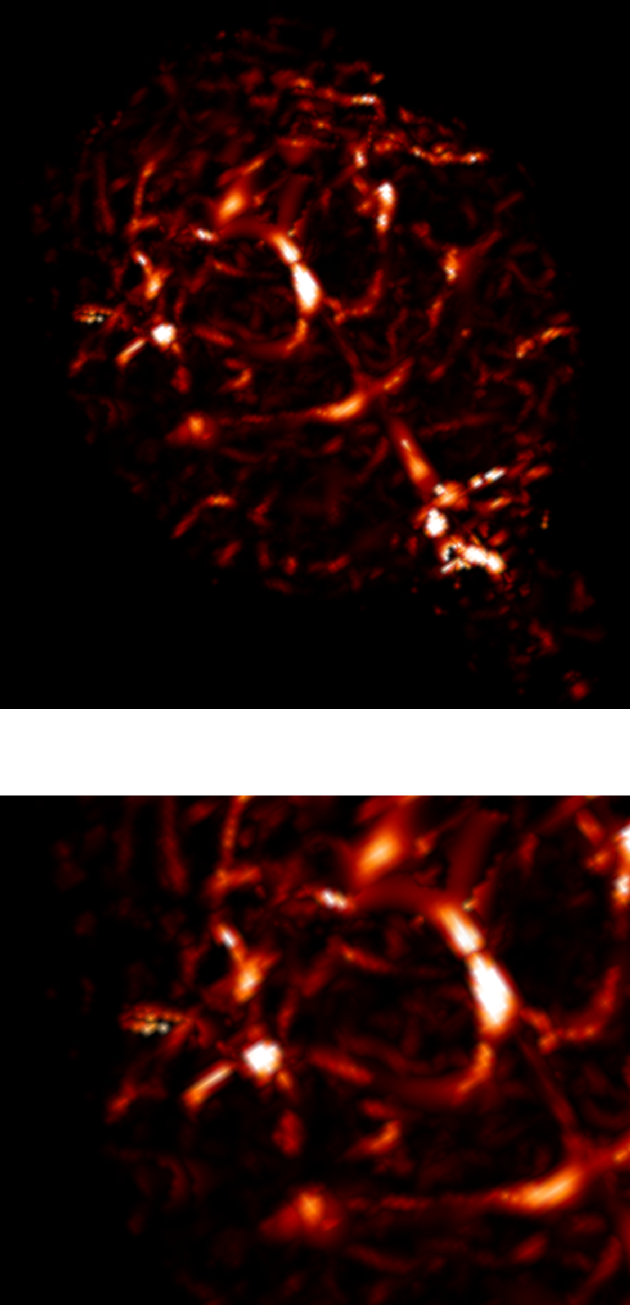

3.2.2 3D angiography

Using the same method as in 2D, namely TSP-sampling and projection onto the set of constraints, we reconstructed volumes from 3D -space. In order to estimate the quality of the reconstructions, we compared the angiograms computed from the 3D images using Frangi filtering [19]. The results are shown in Fig. 3 for acceleration factors (Fig. 3(b,e)) and (Fig. 3(c,f)) and compared to the angiogram computed from the whole data.

Using the strategy described in Part 3.1 the time to traverse -space would be 3.53 s (full acquisition), 3.15 s () and 0.88 s (). The main drawback of TSP-based sampling schemes is that the time reduction is not directly proportional to , in contrast to classical 2D downsampling and reading out along the third dimension. Nevertheless, if the number of measurements is fixed, the TSP-based approach leads to more accurate reconstruction results since the sampling scheme may fit any density [7].

Angiograms shown in Fig. 3 illustrate that one can reduce the travel time in the -space and still observe accurate microvascular structure. If , time reduction is minor (about 10% less), but the computed angiogram is almost the same as the one obtained with a complete -space. It is interesting to notice that with a higher acceleration factor (), the acquisition time is reduced by 75%, but the computed angiogram remains of good quality. The angiogram appears a bit noisier, especially in the pre-injection setting (Fig. 3(c)), but the post-injection image allows recovering Willis polygon and most of the major vessels of the mouse brain (Fig. 3(f)).

| Original (s) | (s) | (s) |

|---|---|---|

| (a) | (b) | (c) |

|

pre-injection

|

|

|

| PSNR=29.0 dB | PSNR=26.6 dB | |

| (d) | (e) | (f) |

|

post-injection

|

|

|

| PSNR=25.5 dB | PSNR=24.1 dB |